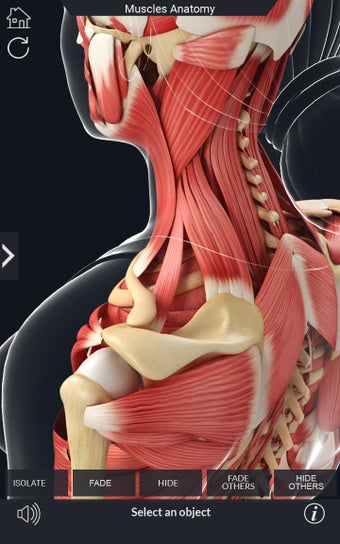

Den mest omfattande mobilappen som finns i världen för att studera muskelanatomi, som låter dig rotera 360°, zooma och flytta kameran runt en mycket realistisk 3D-modell.

Det finns många verktyg tillgängliga för varje muskel, inklusive:

- Rotera 360°.

- Zooma in och ut.

- Flytta kameran runt modellen.